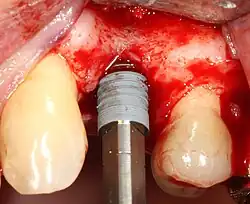

Zavedení implantátu

Většina implantátových systémů má pět základních kroků pro zavádění každého implantátu:[12]:s.214–221

- Odsazení měkkých tkání: Nad hřebenem kosti se provede řez, kterým se silnější přiléhající dáseň rozdělí zhruba na polovinu, takže konečný implantát bude mít kolem sebe silný pás tkáně. Okraje tkáně, z nichž každý se označuje jako lalok, se odsunou, aby se odkryla kost. Zákrok bez laloku je alternativní technika, při níž se pro umístění implantátu místo zvedání laloků odstraní malý úlomek tkáně (o průměru implantátu).

- Vrtání při vysoké rychlosti: Po odsazení měkké tkáně a s použitím chirurgického vodítka nebo stentu se podle potřeby umístí pilotní otvory, a to přesnými vrtáky s vysoce regulovanou rychlostí, aby se zabránilo spálení nebo tlakové nekróze kosti.

- Vrtání při nízké rychlosti: Pilotní otvor se rozšiřuje pomocí postupně se rozšiřujících vrtáků (obvykle tři až sedm po sobě jdoucích vrtacích kroků v závislosti na šířce a délce implantátu). Dbá se na to, aby nedošlo k poškození osteoblastu nebo kostních buněk přehřátím. Chladicí fyziologický roztok nebo vodní sprej udržuje nízkou teplotu.

- Umístění implantátu: Šroub implantátu je zaveden, může být buď samořezný,[29]:s.100–102 nebo se analogicky naklepe do připraveného místa . Poté se zašroubuje na místo momentovým klíčem[32] s přesným krouticím momentem, aby nedošlo k přetížení okolní kosti (přetížená kost může odumřít, což je stav zvaný osteonekróza, který může vést k tomu, že se implantát nedokáže plně integrovat nebo spojit s čelistní kostí).

- Adaptace tkáně: Dásně se přizpůsobí kolem celého implantátu a vytvoří silný pás zdravé tkáně kolem "hojícího se pillíře. Naproti tomu může být implantát pohřben, kdy je horní část implantátu uzavřena krycím šroubem a tkáň je uzavřena tak, aby jej zcela zakryla. K pozdějšímu odkrytí implantátu je pak nutný druhý zákrok.

Aby se implantát oseointegroval, musí být obklopen zdravým množstvím kosti. Aby implantát dlouhodobě přežil, musí mít kolem sebe silný obal ze zdravých měkkých tkání (dásně). Běžně se stává, že buď kost, nebo měkké tkáně jsou natolik nedostatečné, že je chirurg musí rekonstruovat buď před zavedením implantátu, nebo během něj.[29]:s.1084

Rekonstrukce tvrdých tkání (kosti)

Kostní štěp je nutný při nedostatku kosti. Také pomáhá stabilizovat implantát tím, že zvyšuje jeho přežití a snižuje okrajový úbytek úrovně kosti.[37] I když stále existují nové typy implantátů, například krátké implantáty, a techniky umožňující kompromis, obecným cílem léčby je minimální výška kosti 10 mm a šířka 6 mm. Případně jsou defekty kosti odstupňovány od A do D (A=10+ mm kosti, B=7–9 mm, C=4–6 mm a D=0–3 mm), přičemž pravděpodobnost oseointegrace implantátu souvisí se třídou kosti.[38]:s.250

K dosažení odpovídající šířky a výšky kosti byly vyvinuty různé techniky kostních štěpů. Nejčastěji se používá tzv. metoda řízené augmentace kostním štěpem, kdy se defekt vyplní buď přirozenou (odebranou nebo autotransplantovanou) kostí, nebo alotransplantátem (kost dárce nebo syntetická kostní náhrada), překryje se polopropustnou membránou a nechá se zahojit. Během fáze hojení přirozená kost nahradí štěp a vytvoří nový kostní základ pro implantát.[34]:s.223